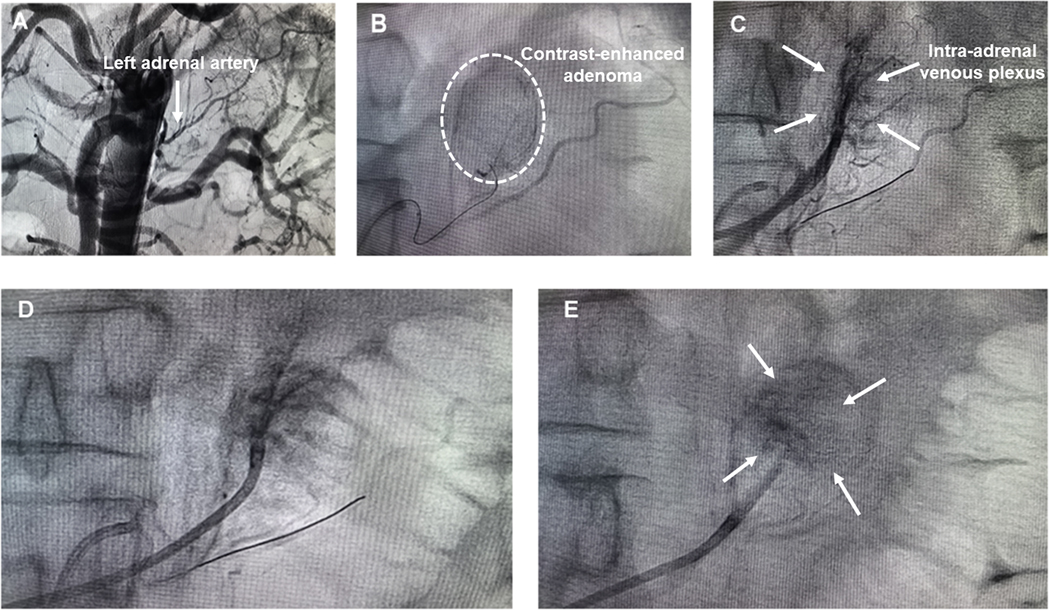

Preoperatively, the patient received antihypertensive therapy with doxazosin (8 mg once daily) and verapamil (240 mg once daily). His blood pressure was maintained at 140–150/78–110 mm Hg with a heart rate of 65–80 beats/min (Table 1). The SAAE procedure was performed through right femoral arterial and venous access under local infiltration anesthesia, as previously reported (15). A 6-Fr Judkins right (JR 3.5) catheter (Launcher, Medtronic, USA) was inserted into the femoral artery through a 6-Fr sheath and the catheter was positioned to abdominal aorta at the level of vertebrae T 12-L 1. Non-selective arteriography was performed to visualize the left adrenal arteries (Figure 3A). A 6-Fr Judkins (JR 3.5) guiding catheter was employed for super-selective cannulation of the left adrenal artery, followed by the insertion of a Fielder XT-R guidewire. After positioning the micro-catheter within the proximal to mid segments of the left adrenal artery, adrenal arteriography was performed to identify the tumor-supplying artery of the aldosterone-producing adenoma (APA) and delineate the entire adenoma staining area (Figure 3B). Concurrently, a second catheter was introduced via femoral vein access and advanced distally into the left adrenal central vein draining functional adenomas, with careful avoidance of the inferior phrenic venous branch. Prudent retrograde venography and adrenal arteriography were performed concurrently to delineate the anatomy of the adrenal venous plexus and the adenoma (Figure 3C). To minimize the risk of anhydrous ethanol backflow entering non-target arteries, the balloon dilation catheter was inflated using a dedicated inflation device prior to anhydrous ethanol injection. For prophylactic analgesia, a 5 mg of morphine was administered intravenously during the procedure. The targeted left adrenal artery was then embolized under fluoroscopic guidance via slow, controlled injection of 2.0 ml of lidocaine followed by 2.0 ml of anhydrous ethanol through a micro-catheter. Post-embolization angiography demonstrated absence of ante-grade flow within the feeding arteries and attenuation of tumor staining, confirming the technical success of the procedure (Figure 3D). To ensure comprehensive embolization of the APA, the catheter was repositioned to the intra-adrenal venous plexus, and balloon-occluded retrograde trans-venous ethanol injection was performed. Specifically, a micro-balloon catheter was positioned in the left adrenal vein. Subsequently, anhydrous ethanol was administered retrogradely under balloon occlusion to induce partial infarction within the APA. Post-procedural venography confirmed markedly reduced opacification of the intra-adrenal venous plexus, indicating successful embolization (Figure 3E). During the SAAE and SAVE procedure, both intra-arterial and intravenous injections of anhydrous ethanol induced acute BP elevation, with blood pressure rapidly escalating to 200/120 mmHg. Sodium nitroprusside infusion was immediately initiated under continuous arterial pressure monitoring. This intervention effectively prevented further blood pressure elevation and achieved a controlled reduction to baseline levels within 3–5 min. Consequently, transient hypertension throughout the entire surgical procedure was successfully managed by intravenous infusion of sodium nitroprusside.

Figure 3. (A) Abdominal aortography; (B) left adrenal arteriography; (C) simultaneous left adrenal venography and arteriography; (D) left adrenal arteriography post embolization; (E) left adrenal venography post embolization.